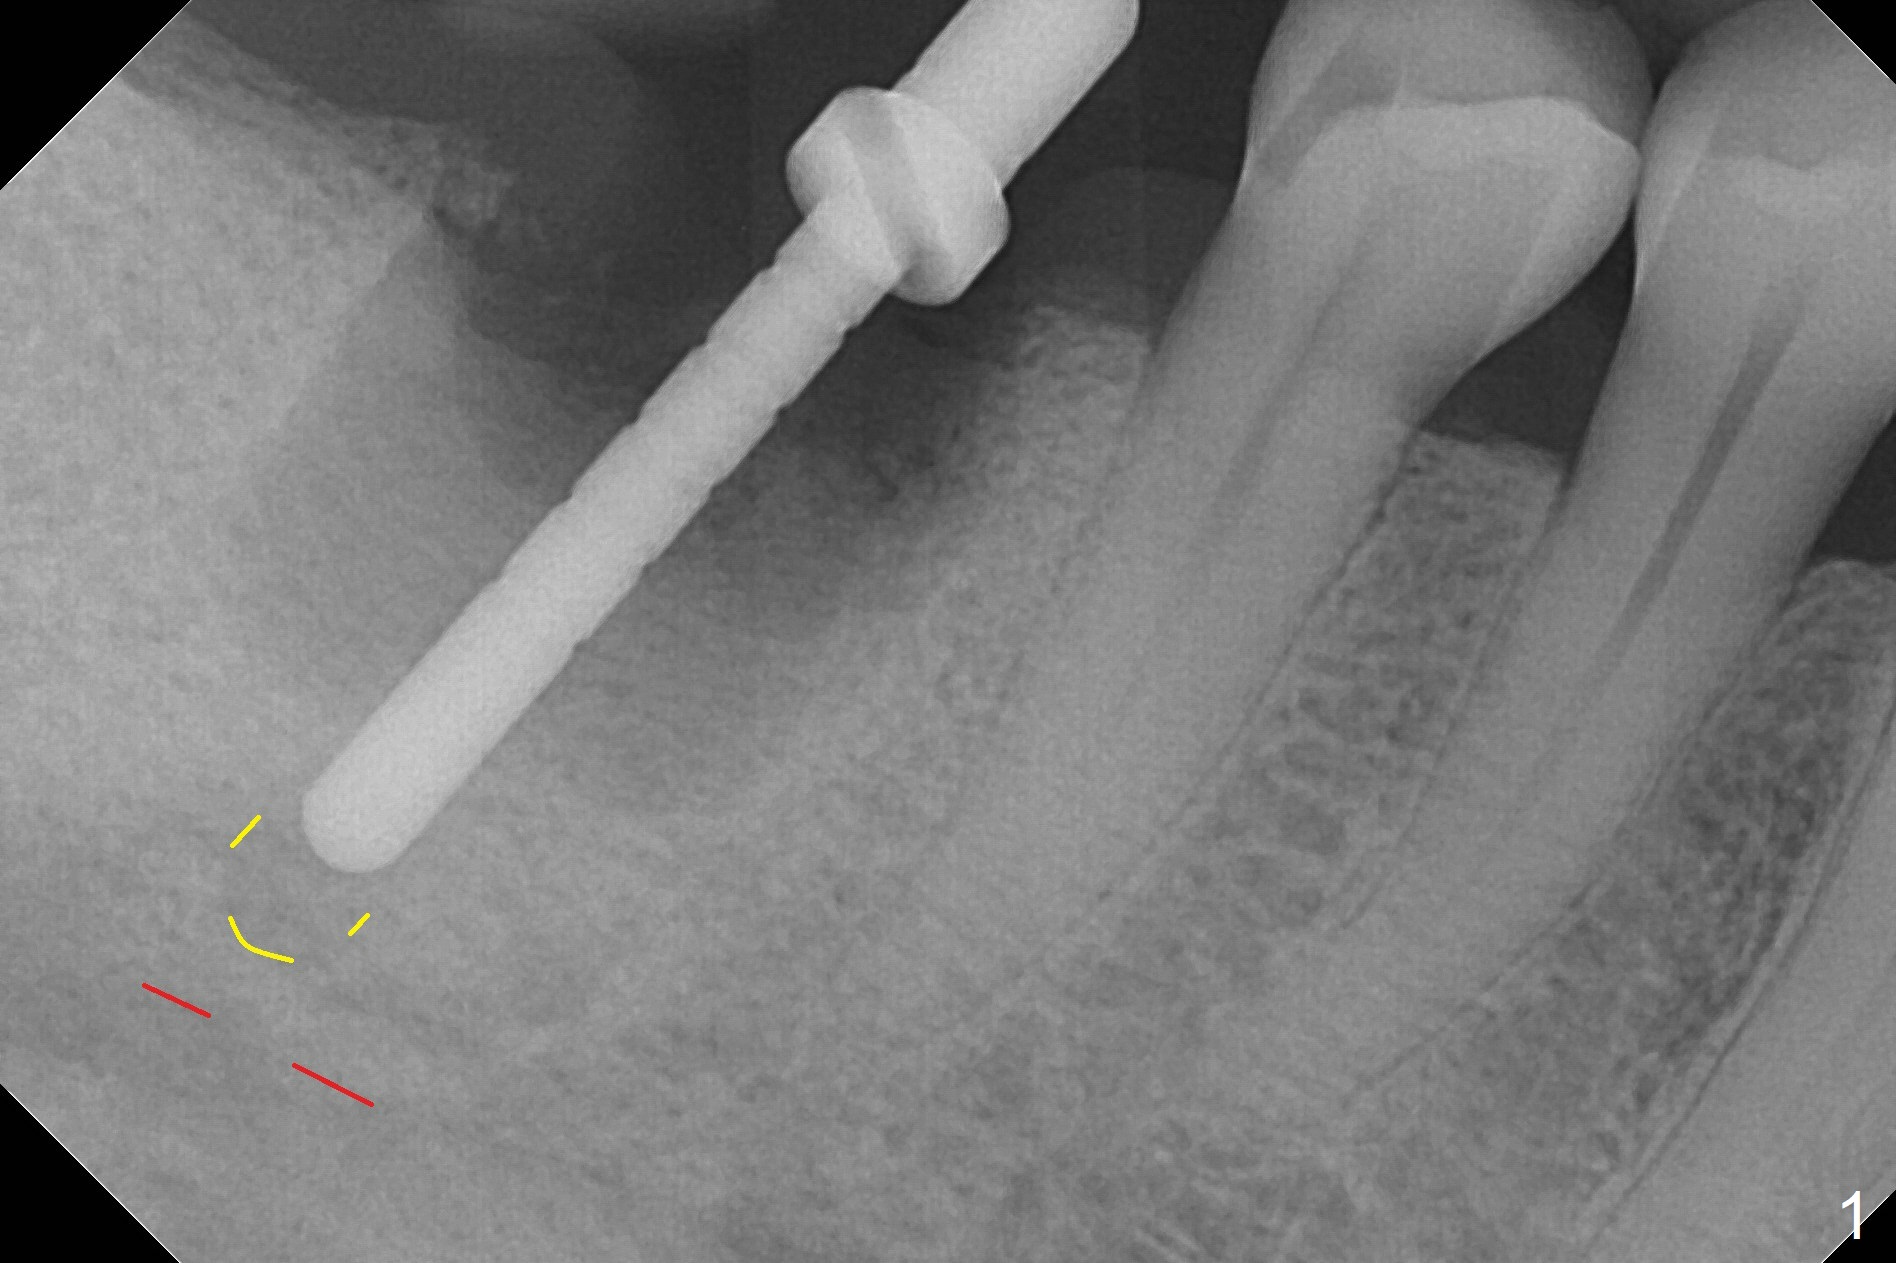

After extraction of the tooth #30 and curettage, the septum becomes so thin that the most coronal portion has to be removed with Rongeur and surgical fissure bur (bone height reduction). Initial osteotomy depth is ~ 4 mm from the flattened septum (Fig.1 (yellow dashed line: apical end of the osteotomy)). Following sequential osteotomy (with intact osteotomy wall), a 6x17 mm tap is placed with apparent clearance from the Inferior Alveolar Canal (Fig.2). When the same size implant is placed with 60 Ncm (Fig.3), the nervous patient feels that the implant is too long (causing pain). CT (Fig.4) and panoramic X-ray (Fig.5) show limited clearance (1.4 mm), but compression of the canal due to high torque could not be ruled out. Since limited amount of the native bone (4.1 mm) for primary stability, the implant is not backed up immediately. Vanilla graft is placed after fabrication of an immediate provisional (Fig.6 *). In brief, immediate implant should be avoided when the septum is thin or the native bone is less than 5 mm (3 mm for primary stability; 2 mm for clearance). In fact the implant has to be untorqued 4-5 times of turn to relieve pain nearly 1 month postop. The patient returns for impression 5 months postop (4 months post implant back up, Fig.7). When the abutment is changed to 5x5 mm and prepared, she reports earache (residual nerve damage?). The patient has had the similar complaint 9 months postop; it appears that there is radiolucency distally (Fig.8 >, as compared to radiopaque mesially (*)). The distal gingiva is tender. With a remade permanent crown, oral hygiene instruction is provided. If necessary, CBCT is taken with possible bone graft.